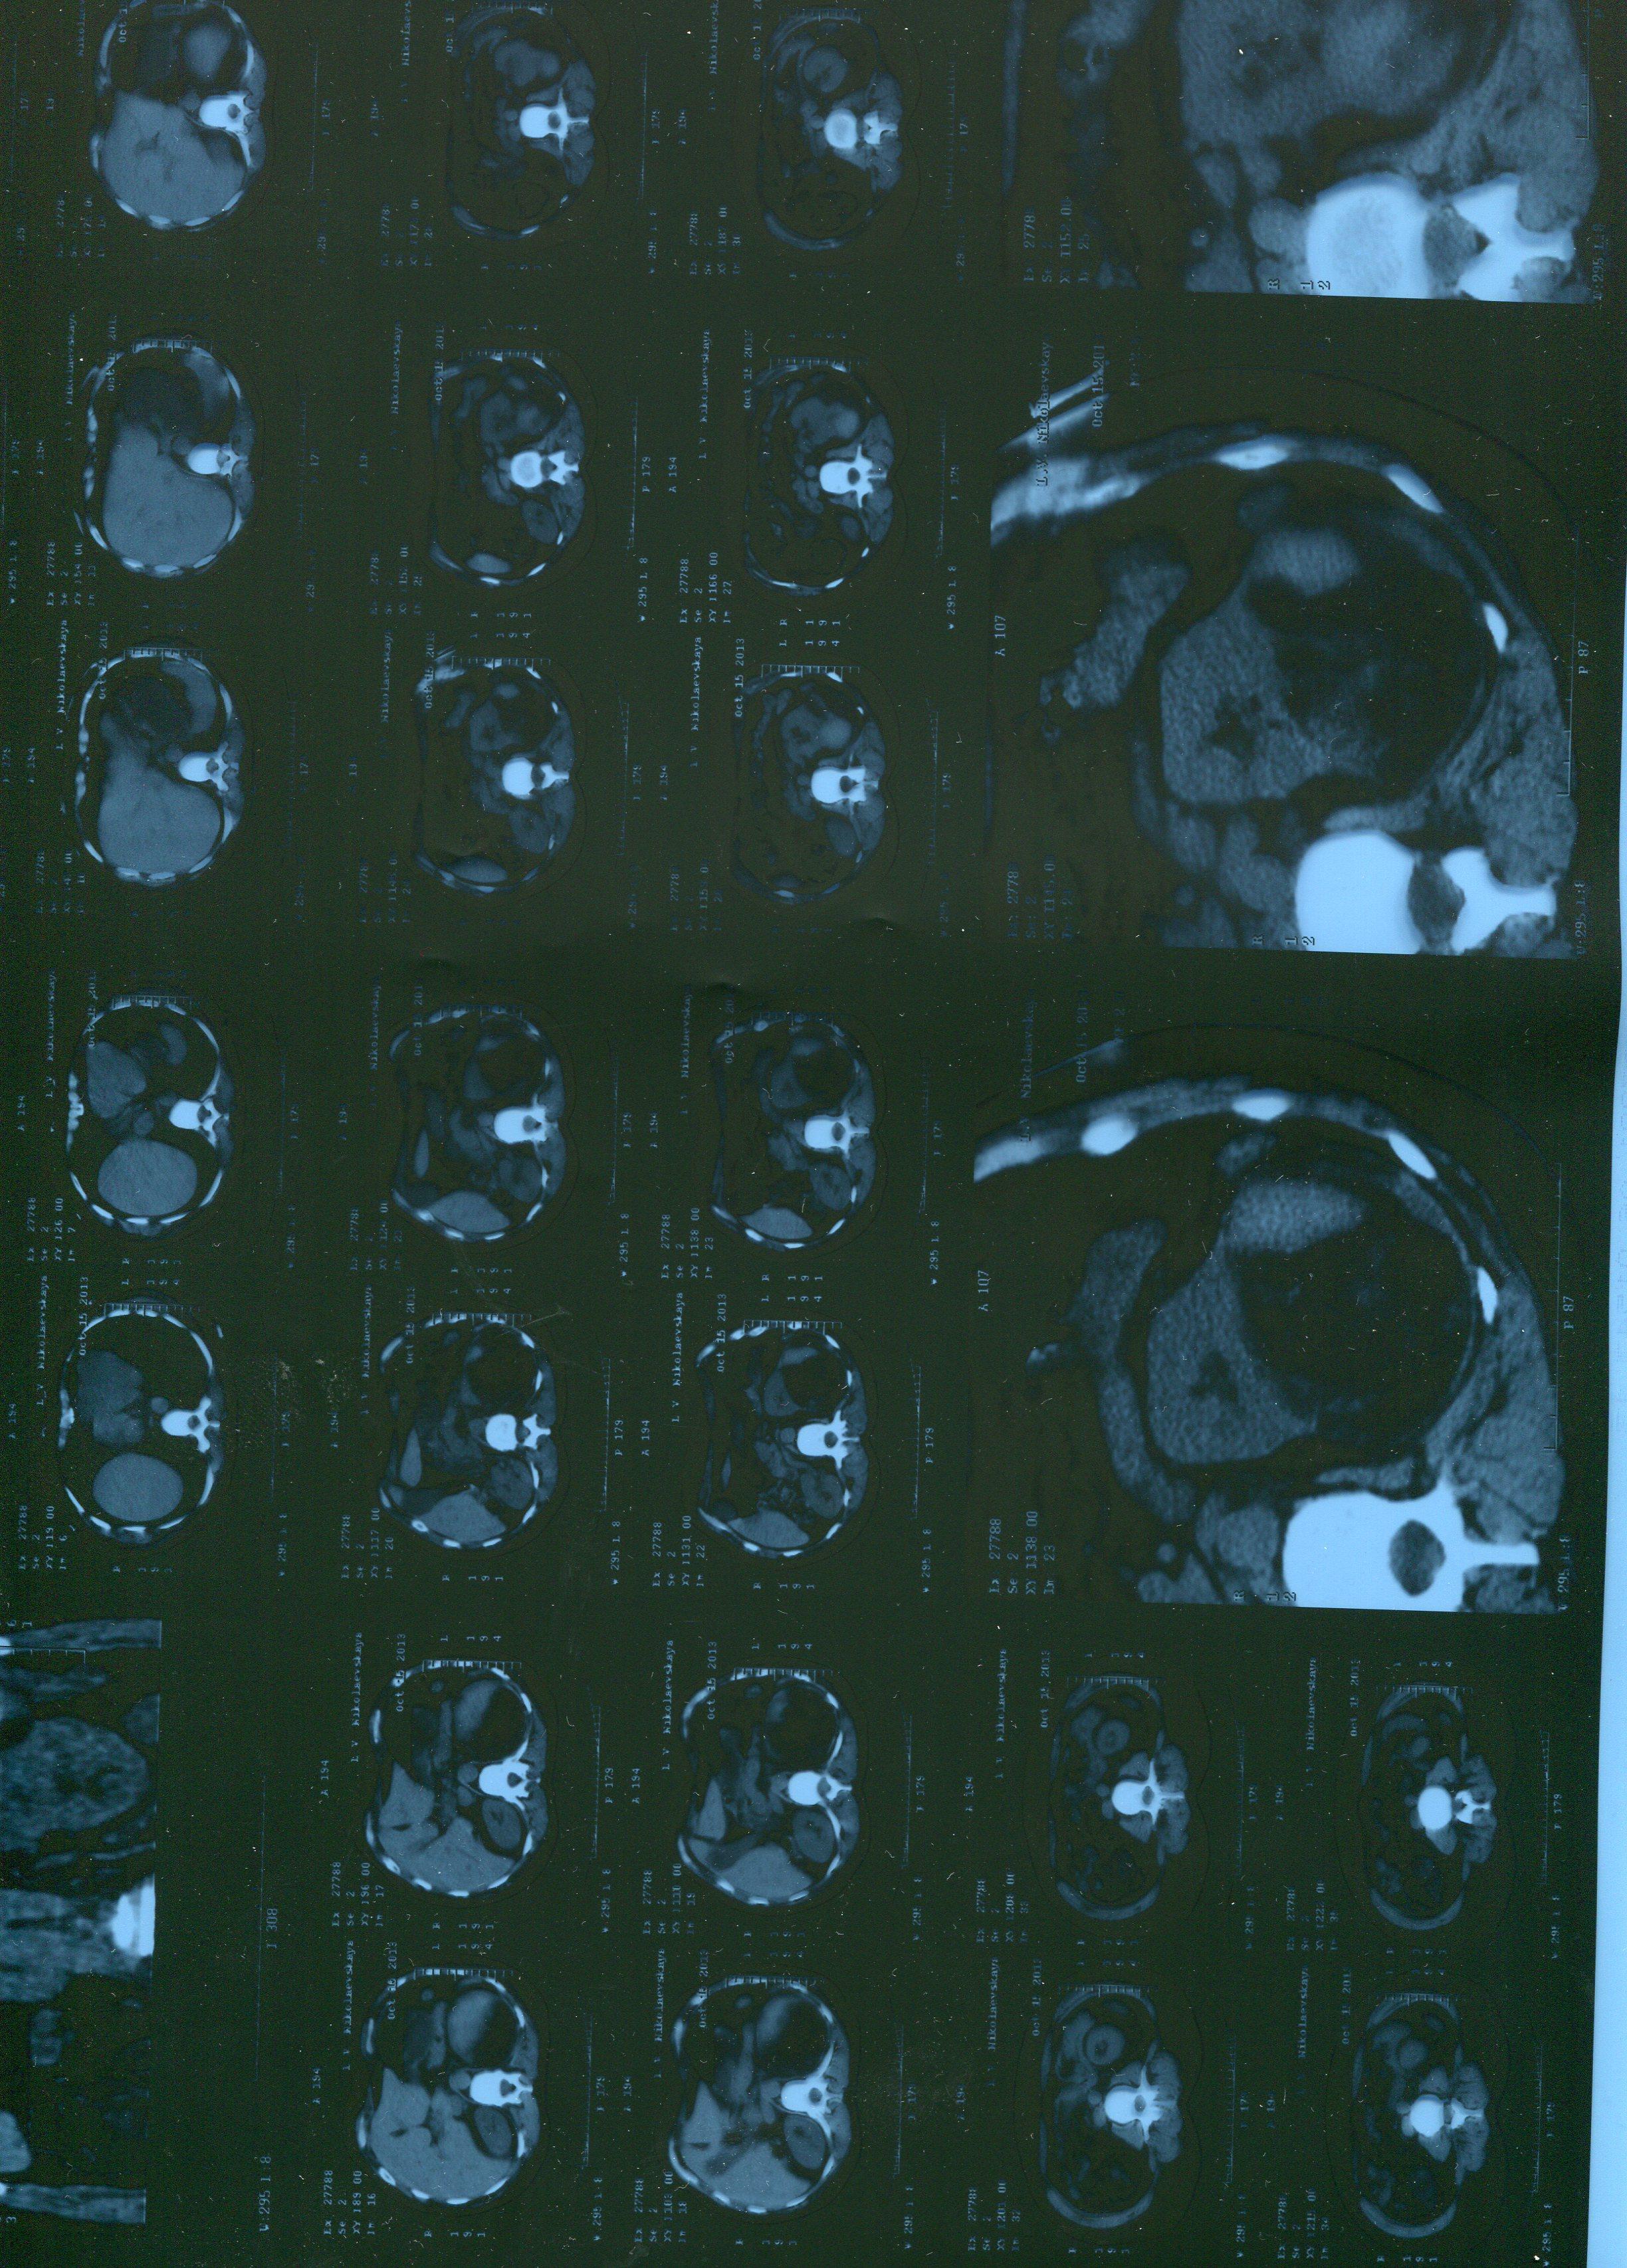

Случайно при обледовании нашли огромное образование в почках . жду госпитализацию. Недавно делала узи почек . ничего не нашли. И вдруг такое. Что вы можете сказать , по этому поводу. я просто в ужасе.

Томограмма дошла в " обрезанном " виде. Пришлите описание(там должно быть указано и состояние лимфоузлов). Пришлите результаты УЗИ.